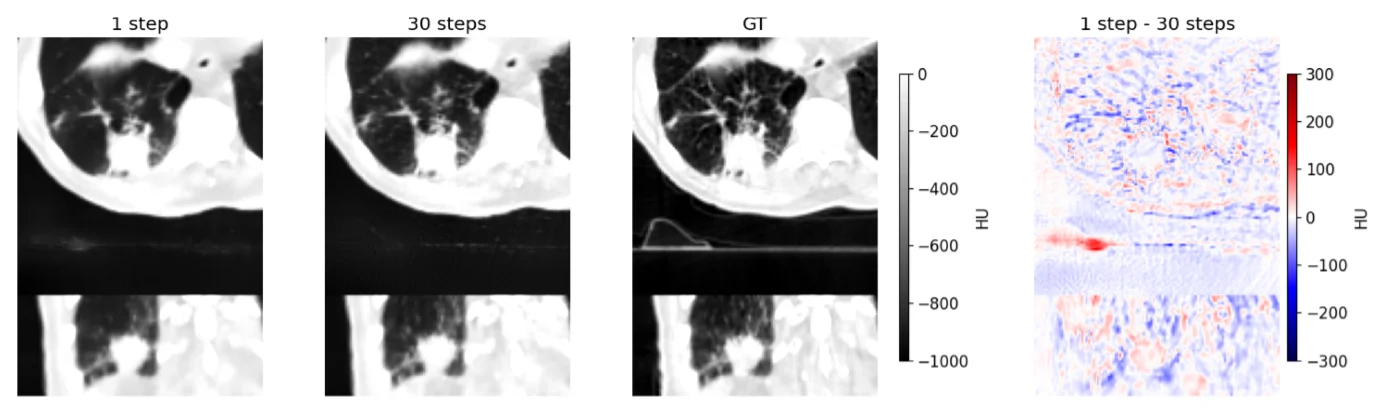

MInDI-3D kombiniert ein U-Net-basiertes Modell mit Attention-Mechanismen und verwendet einen iterativen Prozess, um die Qualität eines sparse-view CBCT signifikant zu verbessern. Im Gegensatz zu herkömmlichen Methoden kann mit MInDI-3D der sog. „perception-distortion trade-off“ explizit durch den Kompromiss gesteuert werden, was so selbst aus wenigen 2D Projektionen hochpräzise 3D-Rekonstruktionen ermöglicht. Für das Training des Modells wurde ein neuartiger groß angelegter Pseudo-CBCT-Datensatz mit mehr als 16.000 Scans erstellt und öffentlich zugänglich gemacht.

Die Performance des Modells wurde anhand quantitativer Metriken, task-basierter Evaluationen wie automatisierter Organsegmentierung, sowie einer qualitativen Überprüfung durch klinische Experten am Yonsei University Hospital in Südkorea umfassend bewertet. MInDI-3D zeigte eine hervorragende Leistung bei der Entfernung von Artefakten und der Wiederherstellung der Bildqualität. Darüber hinaus liess sich MInDI-3D erfolgreich auf verschiedene Scanner-Modelle übertragen, und die klinische Bewertung ergab positive Ergebnisse.